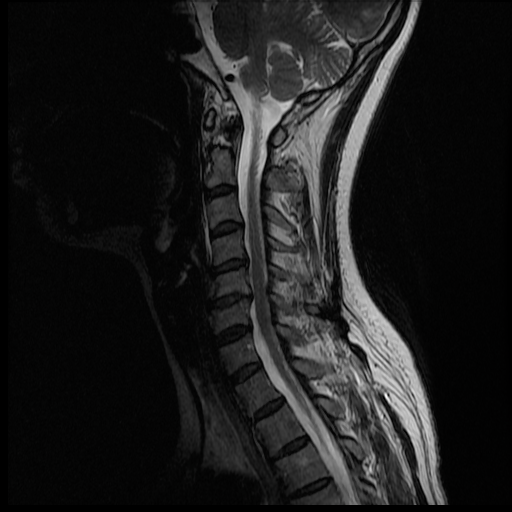

I'm waiting anxiously for Monday morning, but my husband has been pouring over the MRI images most of the night and even this morning. He's not a doctor, but it seems I may have a herniated disc. I hope this is the only thing going on.... The thing is we don't know if this is C6/C7 (where the lesion was seen), or C5/C6. Here are some of the pictures that show that the disc may be bulging/herniated.

Hopefully the experts come to the same conclusion, and that there isn't anything else... only Monday will tell.